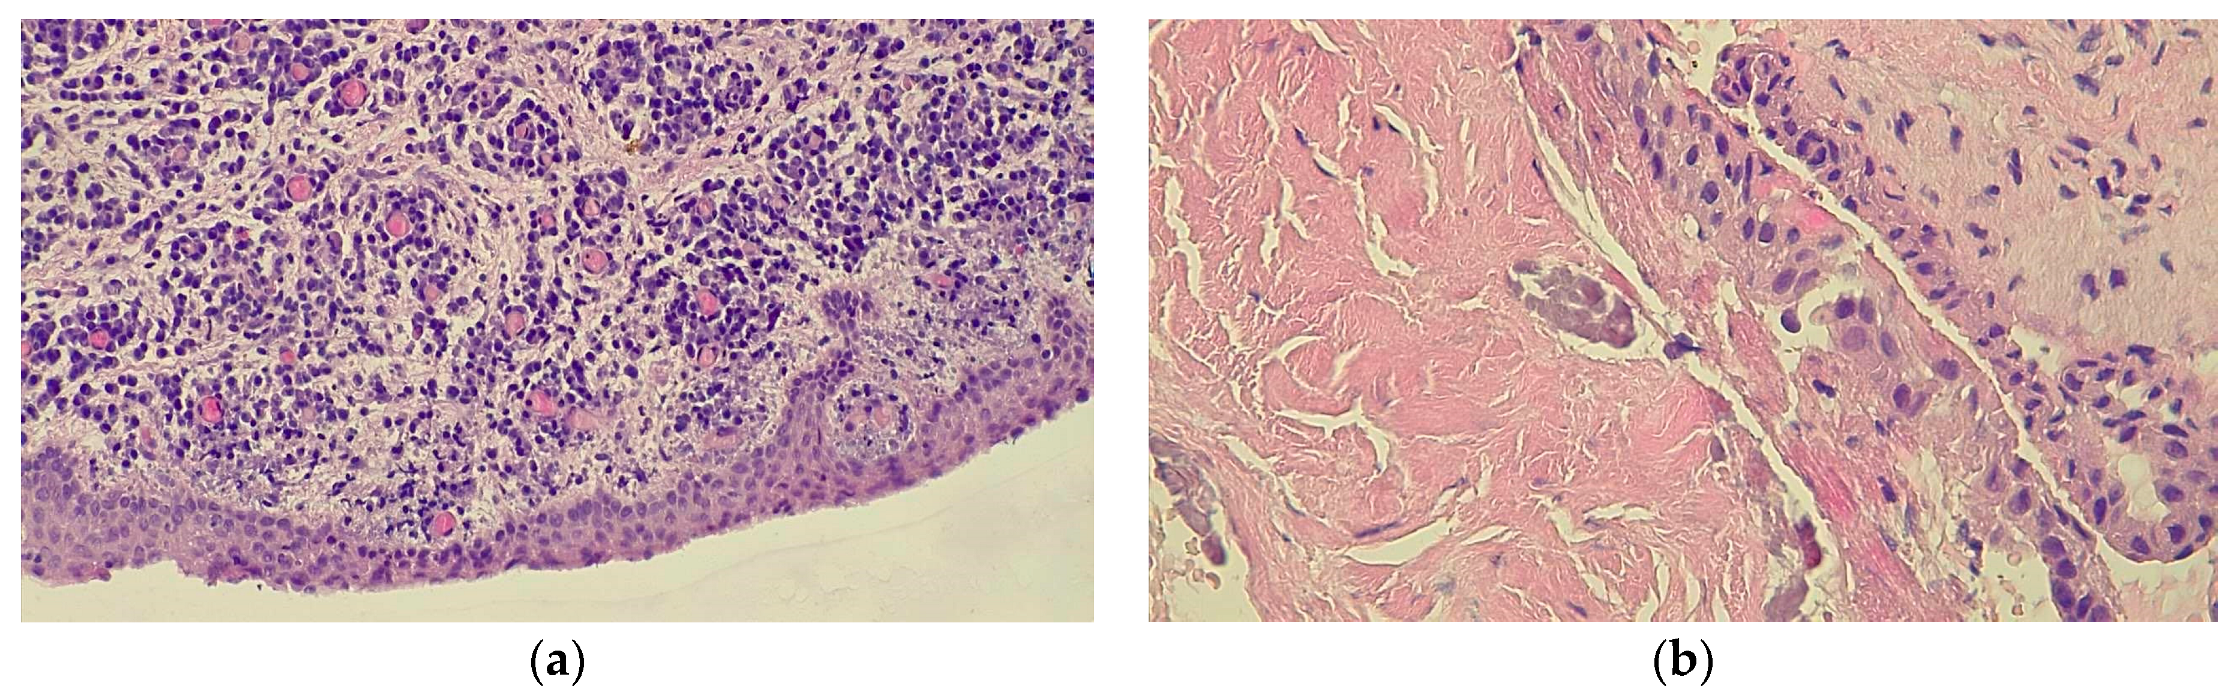

2.2.1. Case 1

2.2.2. Case 2

2.2.3. Case 3